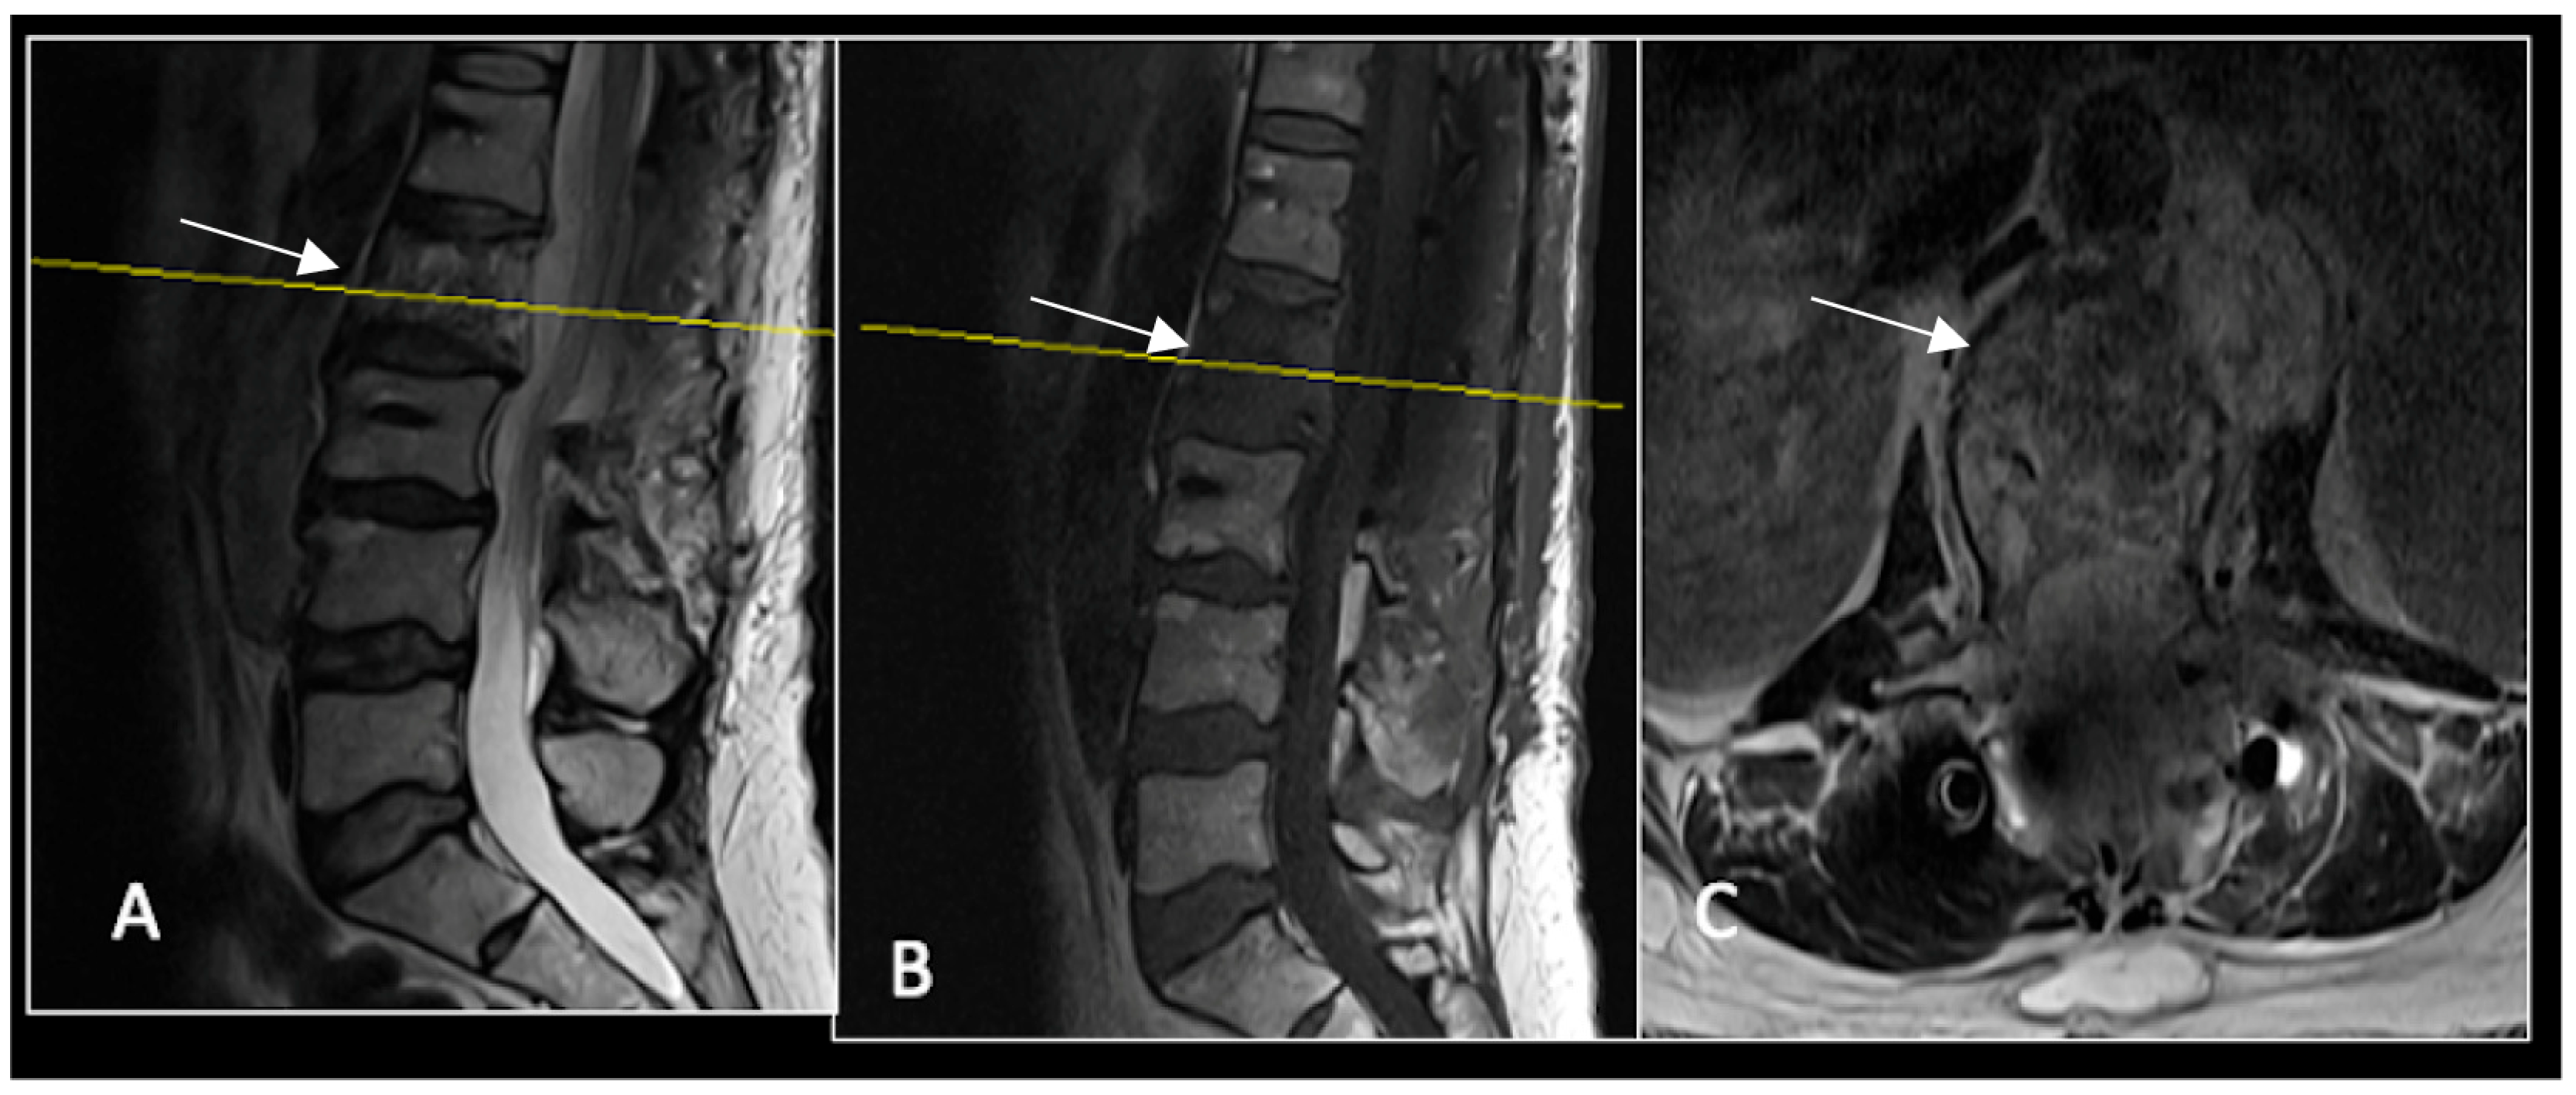

Figure 2.

MRI demonstrating a destructive lobular lesion localised to the C2 vertebra (chordoma) (arrow). There is significant left-sided extension into the paravertebral tissues laterally and epidural space centrally with indentation of the cord. The yellow line on the sagittal images denotes the level at which the corresponding axial section was obtained. (A) T2-W sagittal; (B) T1W sagittal; (C) T2W axial.

Figure 3.

RI post-separation surgery showing reduction in tumour (arrow) dimensions and circumferential decompression. The posterior elements have been removed, and a posterior occipitocervical stablilsation has been performed. En-bloc resection would have necessitated sacrificing the left C2 nerve root and vertebral artery. The yellow line on the sagittal images indicates the level of the corresponding axial section. (A) T2W sagittal; (B) T1W sagittal; (C) T2-W axial.